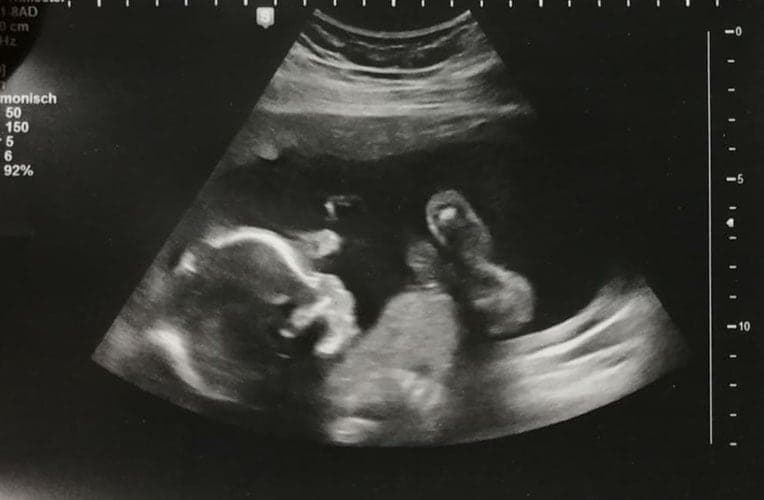

Ultraschallbilder aus dem 2. Trimester (13. bis 28. SSW)

Im 2. Trimester bekommt man oft die schönsten „Ganz-Körper“ Ultraschallbilder. Das Baby ist nun so groß, dass man alles gut erkennen kann und noch nicht zu groß, so dass es noch ganz auf das Bild passt. In dieser Zeit lässt sich meist das Geschlecht bestimmen, wobei manche Babys es einfach nicht preis geben wollen und sich immer so drehen, dass man nichts erkennen kann.